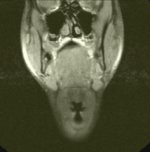

Meine MRT

Aufnahmen: |

MR-Angiographie (MRA) meiner Halsgefäße Stand: 03.03.2006 |